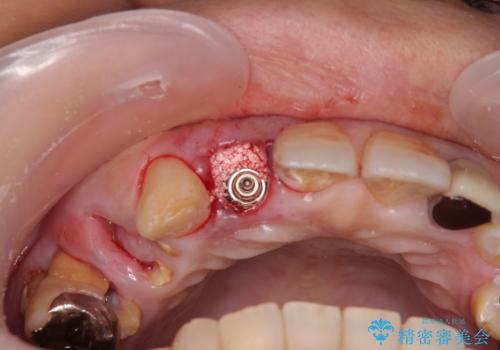

セオリーとしては、インプラント補綴治療により奥歯の咬み合わせを確立してから、前歯部の処置を行うことになりますが、初めてのインプラント治療であることや、前歯部の見た目が気になっていることから、前歯の抜歯即時埋入インプラントによる補綴治療を先行して行い、並行して奥歯のインプラント治療を進めて行くこととしました。

抜歯即時埋入インプラントによる補綴治療の特徴は、短期間であることや処置数が少ないことが挙げられます。また、表側の歯肉の陥凹を避けることができるというメリットがあります。しかしながら、今回は歯根破折の程度が酷く、やや膨らみを失うこととなりましたが、スムーズに治療を終えることができました。